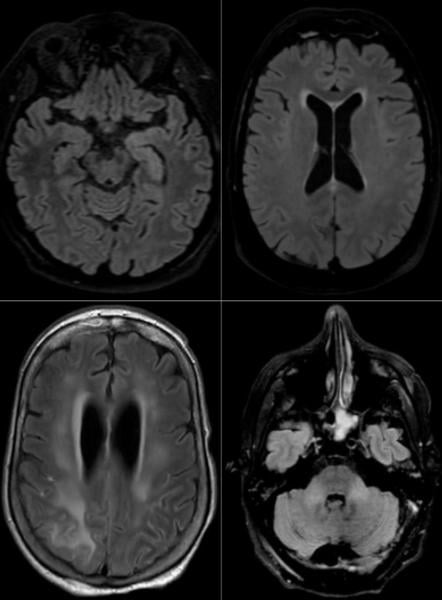

Among the 37 patients included, 28/37 (76%) were associated with one neuroimaging pattern, 7/37 (19%) with two patterns, and 2/37 (5%) showed three patterns. The most frequent MRI findings were: signal abnormalities located in the medial temporal lobe in 16/37 (43%) patients, non-confluent multifocal white matter hyperintense lesions on FLAIR and diffusion sequences, with variable enhancement, with associated hemorrhagic lesions in 11/37 patients (30%), and extensive and isolated white matter microhemorrhages in 9/37 patients (24%).

A majority of patients (20/37, 54%) had intracerebral hemorrhagic lesions and a more severe clinical presentation.

“Three main neuroradiological patterns could be distinguished, and the presence of hemorrhage was associated with worse clinical status. SARS-CoV-2 RNA was detected in the cerebrospinal fluid in only one patient, and the underlying mechanisms of brain involvement remain unclear,” the authors wrote. “Imaging and neurological follow up has to be undertaken in order to evaluate the prognosis of these patients.”